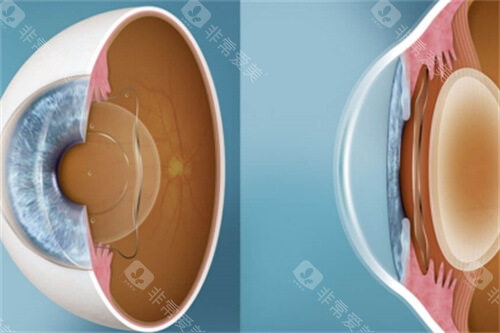

ICL晶体植入手术作为高度近视矫正的主流方案,凭借其可逆性、不损伤角膜的特点,成为越来越多近视患者的选择。

不损伤角膜:适合角膜薄、干眼症等激光手术禁忌人群。

可逆性强:晶体可随时取出,不影响未来其他治疗。